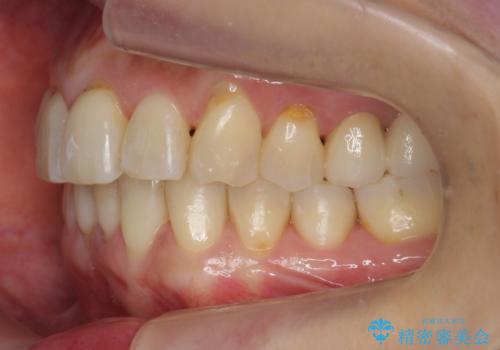

前歯が反対になっている マウスピース矯正+奥歯ブリッジ

- 前歯のがたつきを主訴に来院。

奥歯も少なく、左上奥歯はブリッジにすることになりました。

左下の前歯を中に入れるスペースを確保する目的で左下の奥歯を後ろ移動させました。

また、左下の小臼歯の捻転はマウスピースで治りにくいため、

事前にワイヤーによる部分矯正を行い、矯正用ミニスクリューを植立しています。